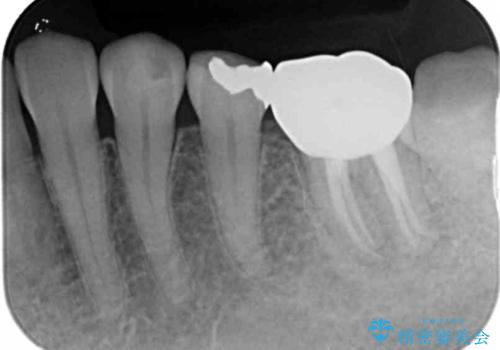

X線写真より根の先に病変が認められたため、根管治療を行ったのちジルコニアクラウンによる咬合機能回復治療を計画します。

根管治療を行ったのち、噛んだときに生じていた痛みも改善し、またしっかりと噛んで食事ができるようになりました。